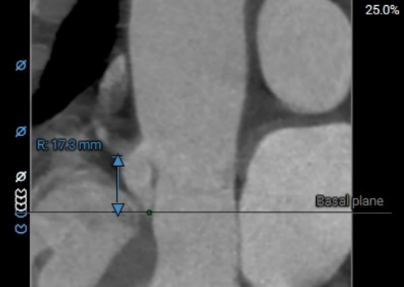

术前主动脉CTA评估:主动脉瓣三叶式,瓣叶基本等大,瓣叶稍增厚,左右瓣叶游离缘轻微钙化;主动脉瓣环周长折算直径约27.6mm;双侧冠脉开口高度可LCA:13.7mm,RCA:17.3mm;左侧冠脉轻度钙化;术中建议造影角度RAO:4°,CAU:22°;降主动脉及双侧髂总动脉轻微钙化,走行迂曲;双侧髂总动脉稍增宽;双侧髂外动脉迂曲。

右冠高度:17.3mm